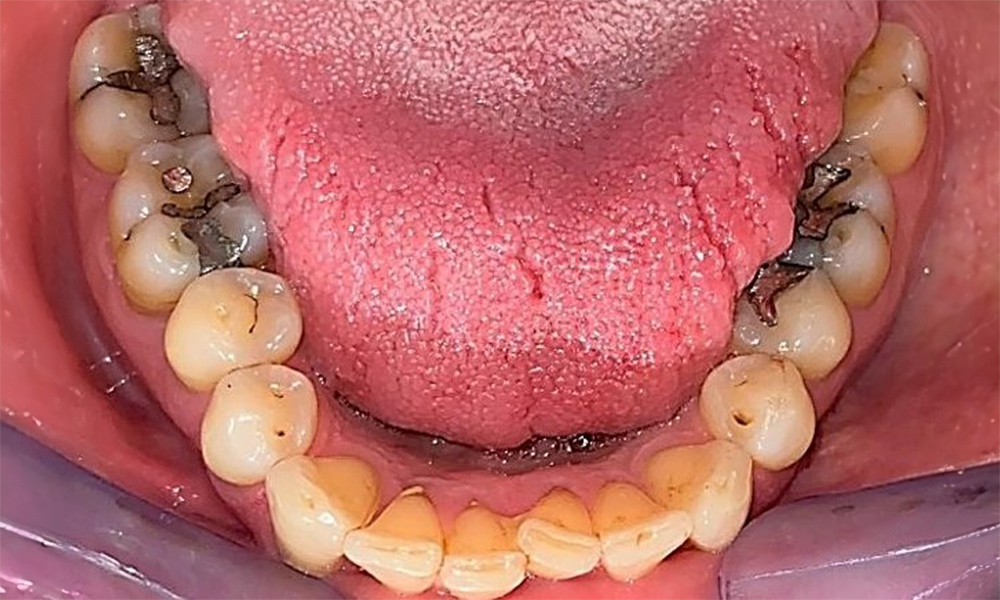

The patient has a full dentition with 28 teeth, which includes amalgam and composite fillings in the molar and premolar regions. There is a visible clinical marginal gap present on tooth 14. Tooth 27 has an adequate gold inlay. There are also generalized attritions and abrasions. (Fig. 2, Fig. 3, Fig. 4, Fig. 5, Fig. 6)

The patient has stage II, grade B periodontitis (5). At 1 to 3 mm, the clinical probing depths were within the physiological range. Localized probing depths of 5 mm were observed on the mesiopalatal aspects on both 17 and 27. There are generalized recessions of 1–3 mm with partial loss of the interdental papillae (Fig. 2, Fig. 3, Fig. 4)